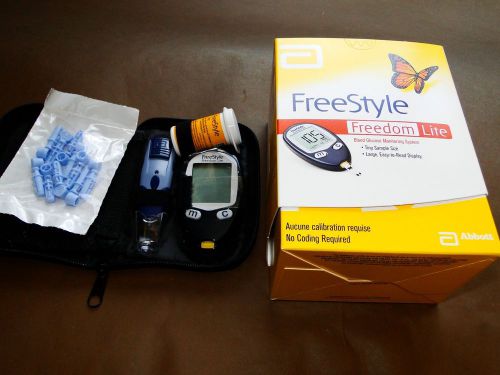

Blood Glucose Monitor Meter System + Test Strips + Lancets BRAND NEW FreeStyle